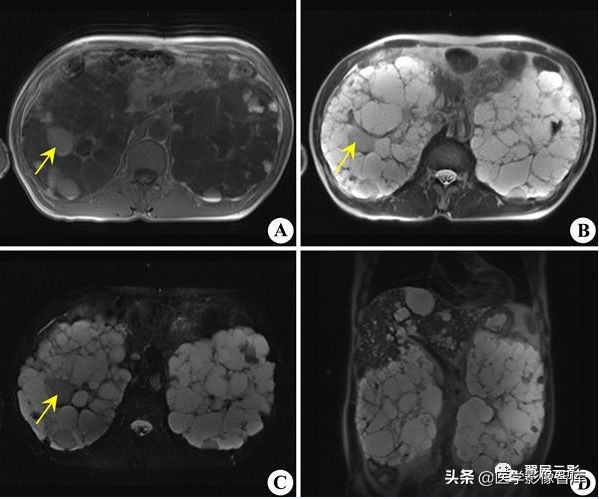

多囊肾

本病常合并多囊肝,此为先天性常染色体显性遗传性疾病,多数学者认为多囊肝是在多囊肾的基础上基因突变的结果,并定位于16号染色体上,也有学者认为该病是由于胚胎发育不良所导致,于胚胎早期管道形成时排列失常,造成无数迷管,于胚胎晚期未退化,且逐渐扩张成囊,成多发性囊肿病,根据发病年龄的不同,将其分为儿童型和成人型,本病多发生于双侧肾脏,可继发感染,结石以及囊内出血和囊壁钙化,也可以恶变,并有阻塞性黄疸及合并皮下囊肿的报道,临床上早期无症状,就诊时肾脏功能已经不同程度受损,肝功能受损程度较轻。

MRI表现为双肾增大和分叶状轮廓,多发囊肿多数为长T1长T2信号,出血性囊肿可为短T1长T2信号或长T1短T2信号,增强扫描所有病灶均不强化,应同时观察合并的多囊肝及胰脾多发囊肿。